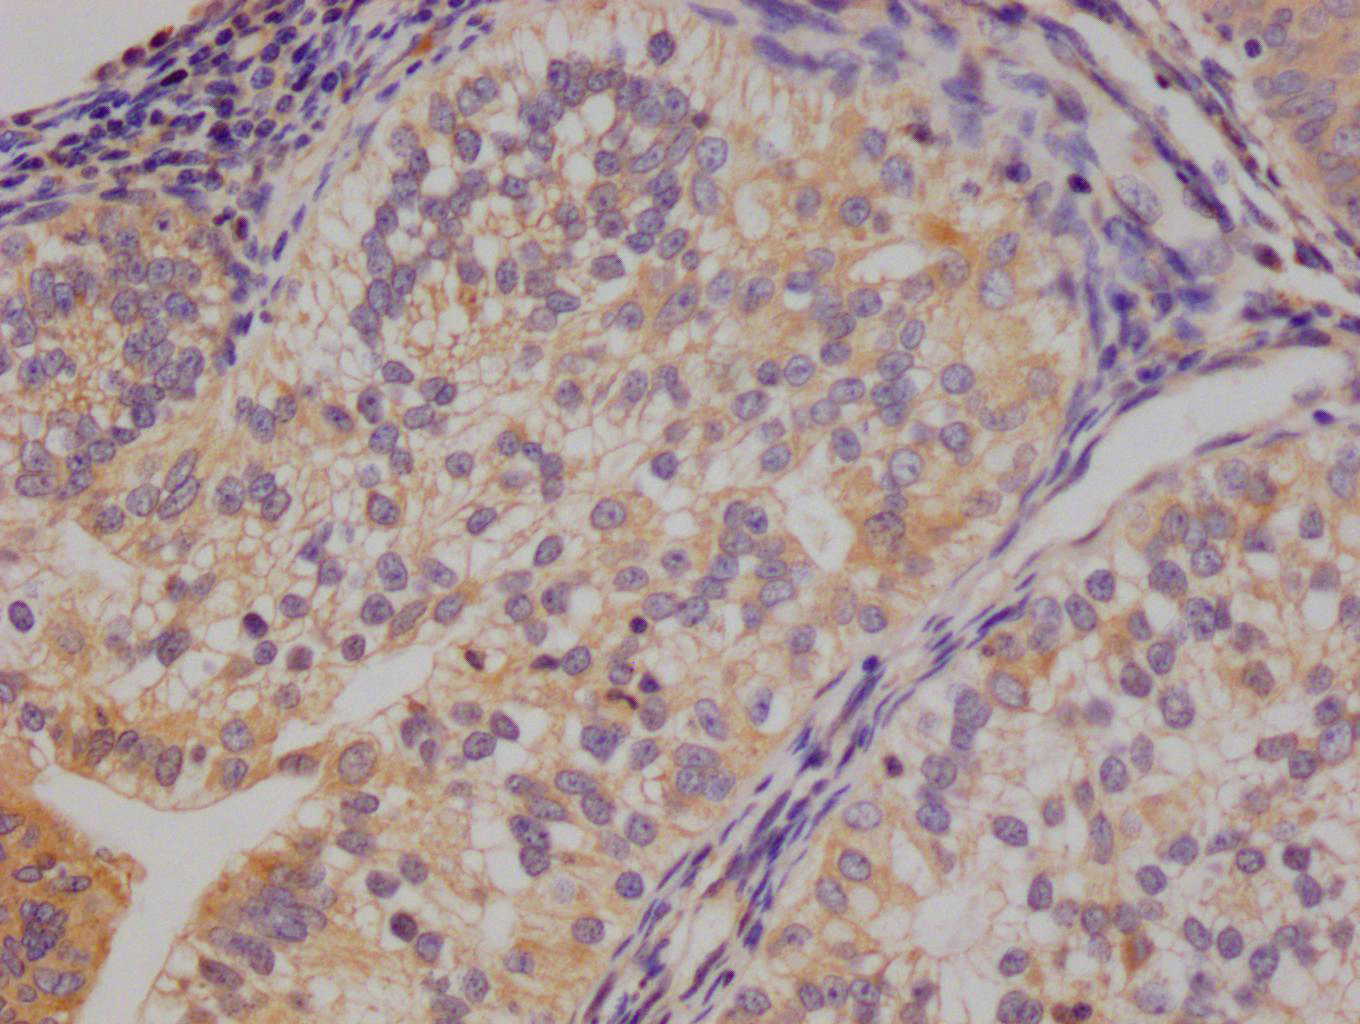

應用范圍:IHC,ELISA

Application Recommended Dilution IHC IHC-p:1:50-300 ELISA 1:10000-20000 -